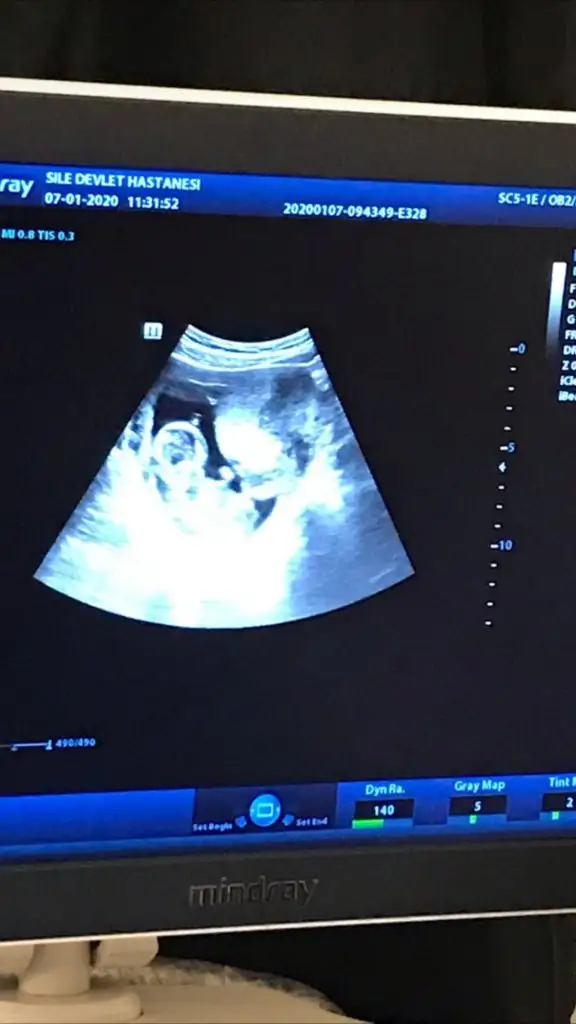

dr soylemeden siz gorun genital nub teorisi ( bebegin cinsiyeti)

O gözüken nub mu emin olamadım ama yine de bir atayım belki fikir yürüten olur didimm.

10+5 günlük bir kurbağa 🐸 🐣

Ne dersiniz?? Ikra meyra Ikra meyra